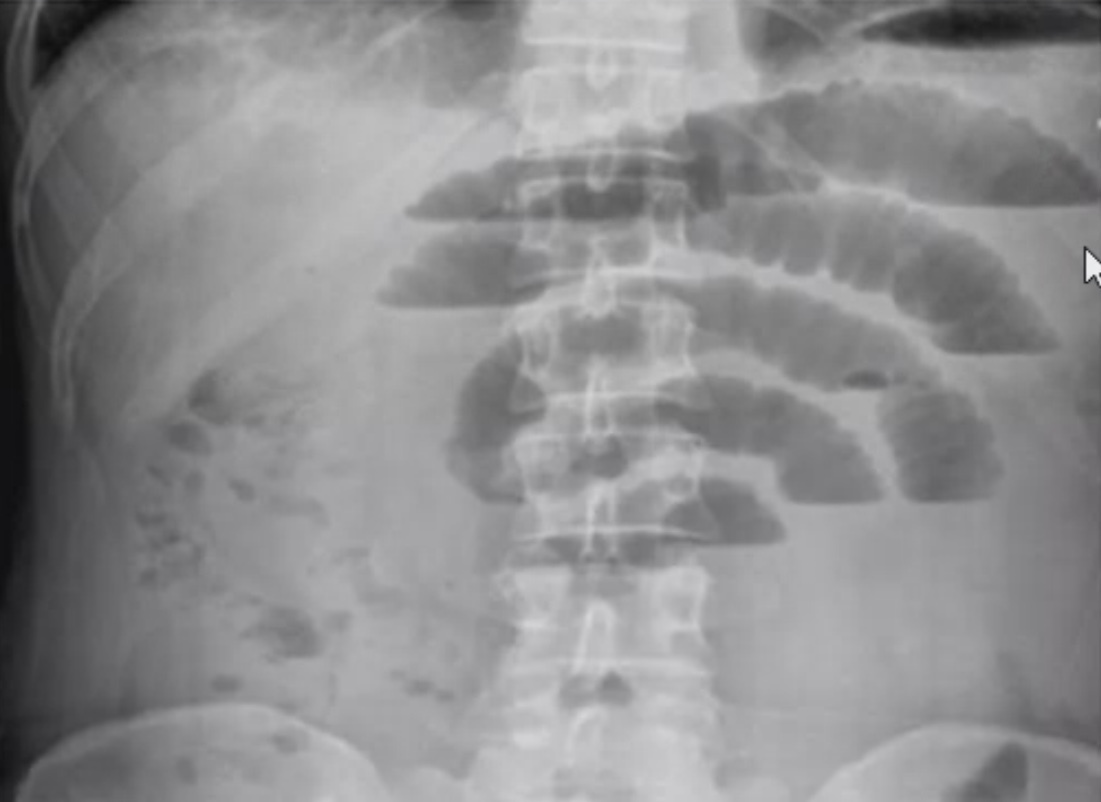

Qual o diagnóstico?

Obstrução intestinal alta

(empilhamento de moedas + aspecto central no Raio-x)